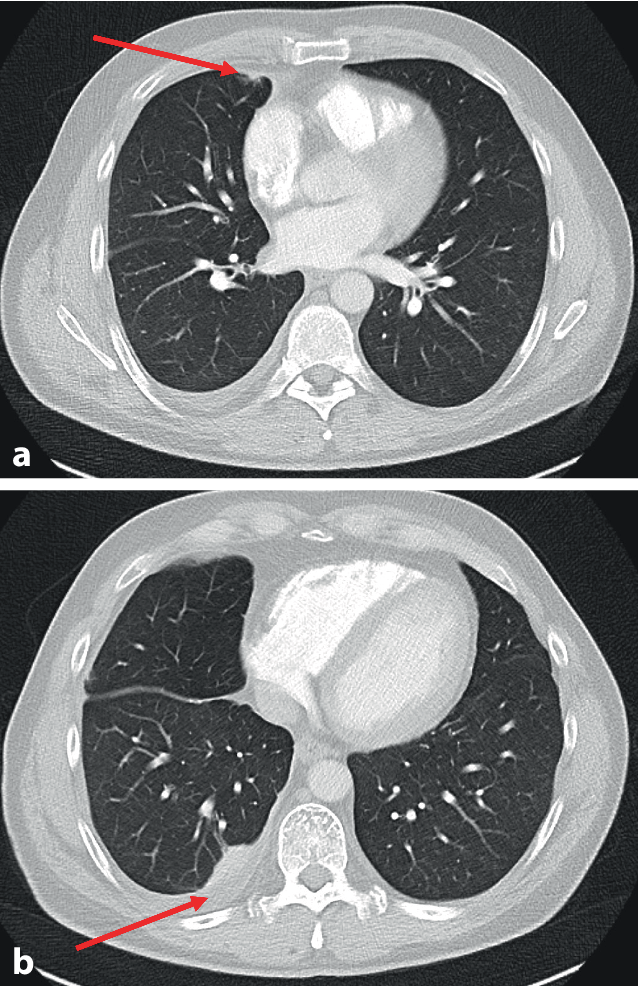

Radiologisch war erneut ein geringer Pleuraerguss rechts nachweisbar. Zusätzlich wurden eine Atelektase im dorsalen Oberlappen rechts, apikale Schwielen beidseits, vermehrte nichtpathologische mediastinale Lymphknoten und eine subpleurale rundherdartige Verdichtung im Mittellappen nachgewiesen (Abb. 1). Eine Pulmonalarterienembolie konnte nicht nachgewiesen werden. Die Oberbauchsonographie war unauffällig. Eine Positronenemissionstomographie konnte keine auffällige Speicherung nachweisen. Eine Bronchoskopie ergab eine Neutrophilie in der bronchoalveolären Lavage (BAL), pathogene Erreger konnten kulturell nicht angezüchtet werden. Die Ziehl-Neelsen-Färbung und MB-TBC-PCR (M. tuberculosis PCR Kit, Geneproof, Brno, Czech Republic) aus dem Bronchialsekret blieben negativ. Maligne Zellen waren ebenso nicht nachweisbar.

Abb. 1

Computertomographie (CT) des Thorax. a Rundherdartige Verdichtung im Mittellappen (Pfeil). b Pleuraerguss mit angrenzender Atelektase (Pfeil)